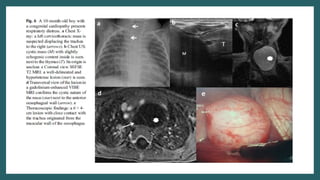

CT Scan on Follow

up

(12 months of age)

Readmission(14/12/23-27/12/23)

• Patient readmitted in Pediatric Surgery and repeat USG was done.

Surgery done on

22/12/23

CT Scan onFollow up (12 months of age)

Readmission(14/12/23-27/12/23) • Patient readmittedin Pediatric Surgery and repeat USG was done.